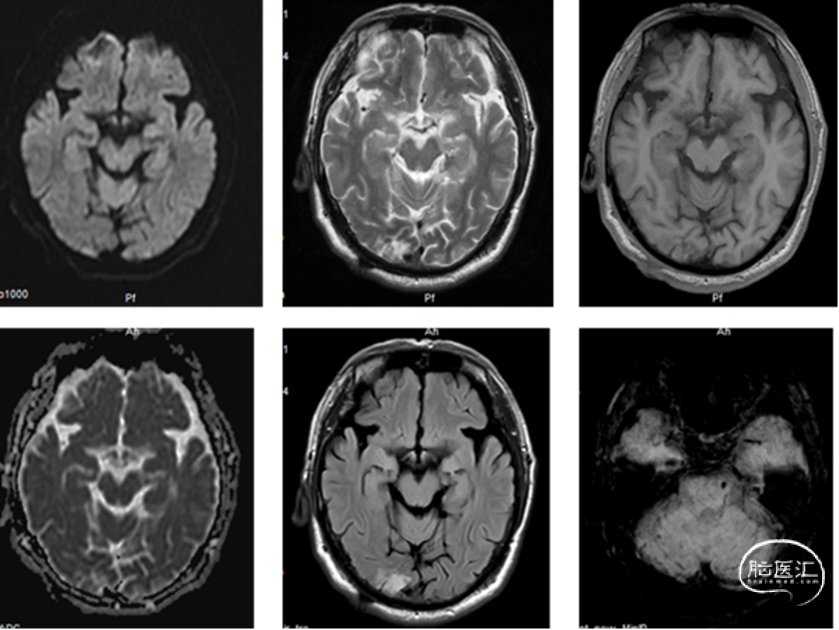

外院磁共振及头颈部CTA示:1、腔隙性脑梗死;2、椎基底动脉重度狭窄。

DSA提示:双侧颈内动脉及颅内血管未见明显狭窄,右侧椎动脉优势,左侧椎动脉纤细,V4段闭塞。右侧椎动脉起始处重度狭窄,右椎V4段及基底动脉近端局限性重度狭窄。患者反复间断发作头晕,考虑后循环缺血引起的TIA发作,且强化药物治疗效果不佳,有介入治疗适应症。